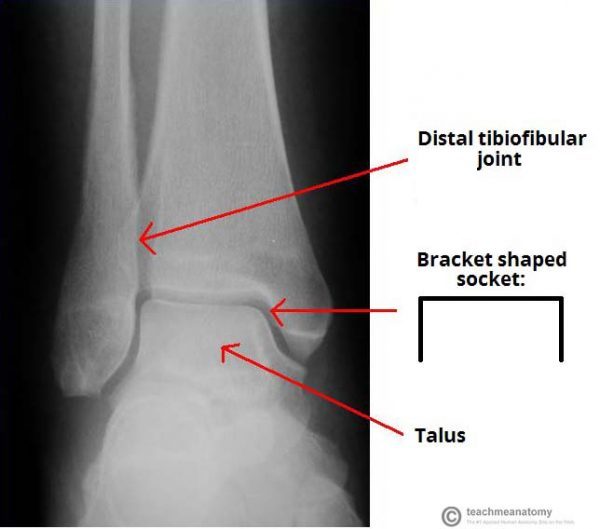

Formed by the tibia, fibula and the talus.

The tibia and fibula are bound together by strong tibiofibular ligaments. Together they form a bracket-shaped socket, covered in hyaline cartilage. This socket is known as the mortise.

The body of talus fits snugly into the mortise formed by the bones of the leg. The talus is wedge-shaped (broad anteriorly and narrow posteriorly).